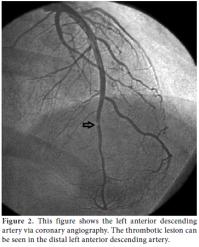

During the clinical follow-up period, the patient's ECG showed dynamic anterior ST-T changes in the precordial derivations (Figure 1), and repeat measurements of these markers revealed a typical course of ACS that featured a relevant rise and fall in TnI. Therefore, the patient underwent coronary angiography which revealed a distally occluded left anterior descending coronary artery (Figure 2). Percutaneous transluminal coronary angioplasty was performed on the occluded site, and because of the thrombotic view of the lesion with a remnant of 30% stenosis accompanied by thrombolysis in myocardial infarction (TIMI) three flow, medical therapy with tirofiban infusion was prescribed for up to a period of 24 hours instead of stent implantation.